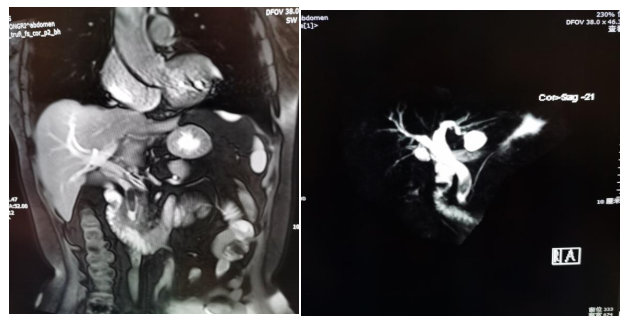

肝脏血管瘤

磁共振胰胆管水成像(MRCP)

胆总管结石(MRCP)